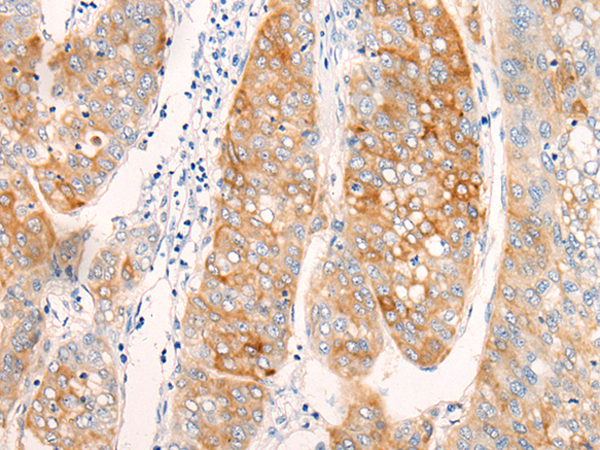

IHC positive control: |

Human liver cancer |